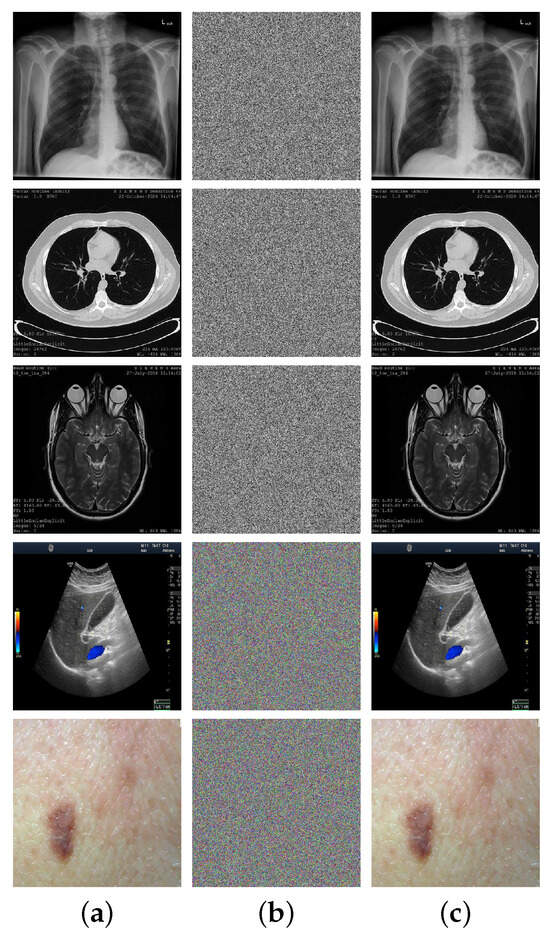

4.1. Visual Evaluation